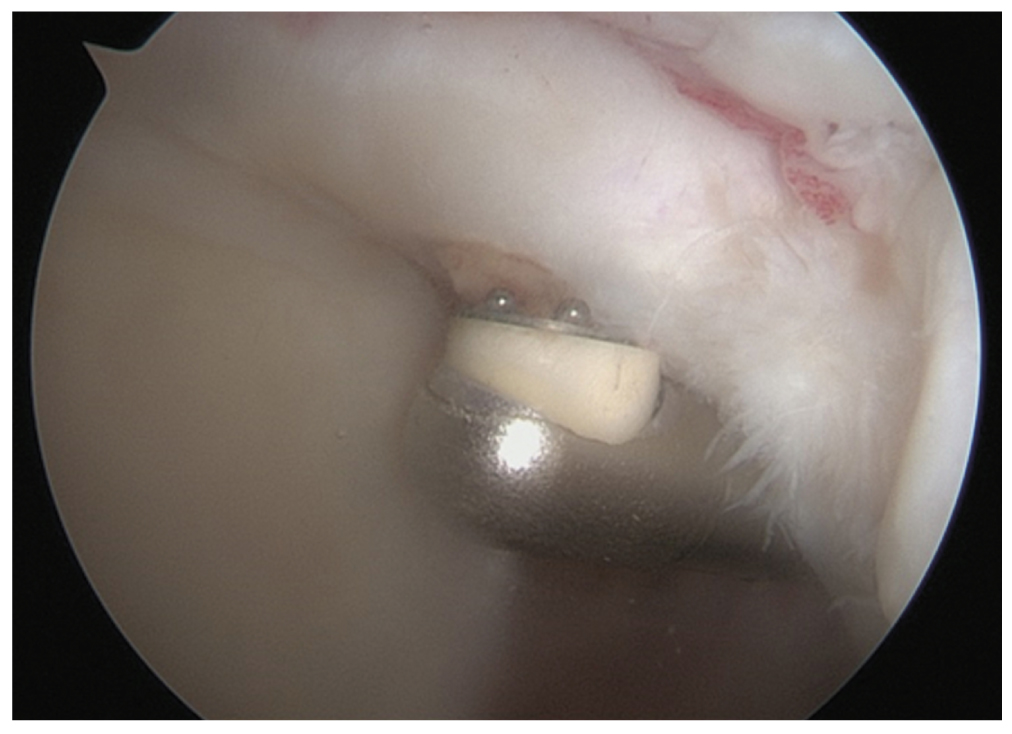

В одном случае выявлен массивный невосстанавливаемый разрыв сухожилия вращательной манжеты плеча, в связи с чем была осуществлена имплантация субакромиального спейсера [14] (рис. 3).

Рис. 3. Этапы имплантации субакромиального спейсера в связи с массивным разрывом сухожилий вращательной манжеты плеча. / Fig. 3. Stages of implantation of a subacromial spacer in the case of a massive rotator cuff rupture.